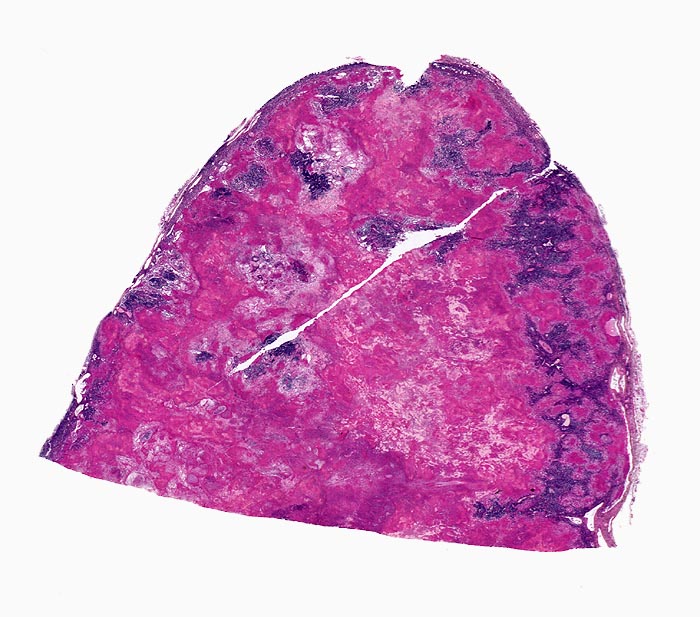

Morphologische Merkmale:

• Lymphknoten mit ausgedehnten konfluierenden eosinophilen Nekrosezonen und nur wenig erhaltenem Lymphknotengewebe (blau).

• In den grösseren Nekrosearealen sind Kerntrümmer von neutrophilen Granulozyten erkennbar.

• Demarkierung der Nekroseareale durch schlanke Epitheloidzellen, Riesenzellen vom Langhanstyp mit hufeisenförmig angeordneten Kernen und Lymphozyten.